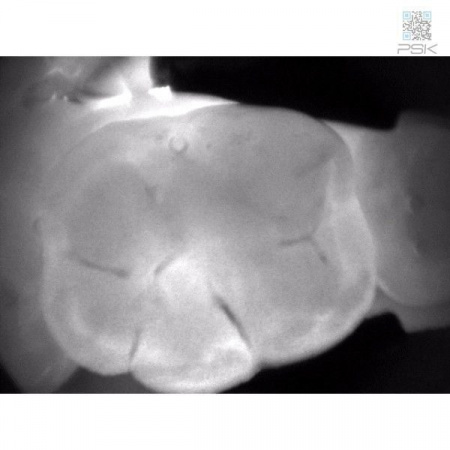

KaVo DIAGNOcam дает Вам полную уверенность в точности результата диагностики. С его помощью Вы сможете обнаружить кариозные поражения на самом раннем этапе развития.KaVo DIAGNOcam позволяет визуализировать их на аппроксимальных и окклюзионных поверхностях зубов и обеспечивает проведение диагностики вторичного кариеса (при небольшом размере пломбы).

Весь секрет заключается в технологии DIFOTI™ за счет генерируемого прибором трансилюминационного (трансиллюминация - яркое сквозное освещение) лазерного излучения в нерентгеновском диапазоне волн. Если объяснять это простым языком, то это – излучение, занимающее диапазон между видимым светом и рентгеновским диапазоном, которое проходит сквозь твердые ткани зуба, при этом области, не пропускающие свет (например, области кариозного поражения) отображаются в виде затемненных на общем фоне участков.

Цифровая видеокамера фиксирует результат и передает изображение на экран в режиме реального времени.

Рентгенограммы и снимки, полученные с помощью KaVo DIAGNOcam, относятся к методам диагностики, прекрасно дополняющим друг друга. С помощью рентгенологической диагностики Вы в дальнейшем сможете беспрепятственно проверить и дополнить данные KaVo DIAGNOcam, исключив часть рентгеновского излучения для пациента. На снимках отчетливо визуализируются структуры коронковой части зуба, располагающиеся выше уровня десневого края. Таким образом, становится возможным раннее распознавание кариеса и проведение профилактического, малоинвазивного лечения. Ваши пациенты будут в восторге!Удобный и информативный план лечения для Ваших пациентов